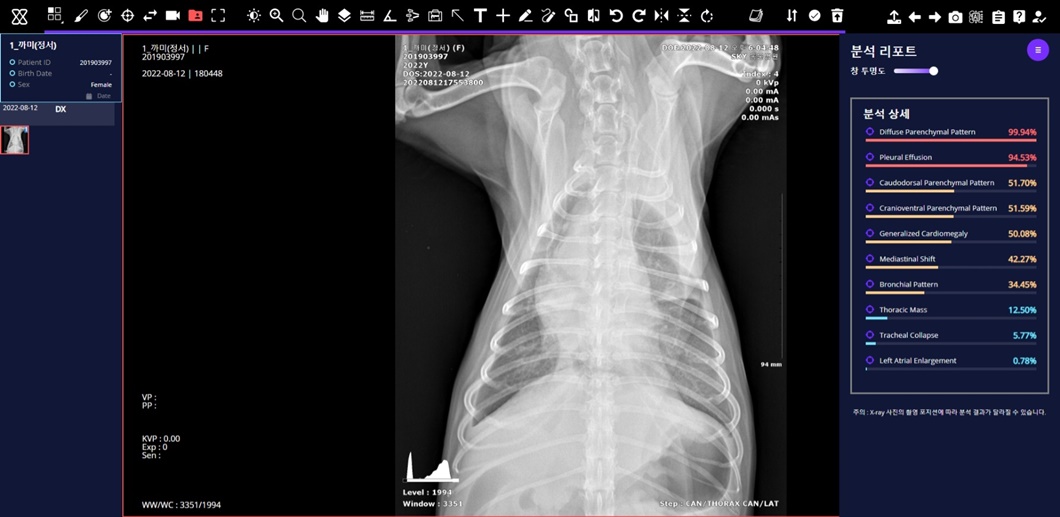

세부적으로는 ▲반려견 근골격 이상 영역 7종 검출모델 평균 질환탐지율(민감도)* 86% ▲반려견 흉부 이상 패턴 10종 분류모델 평균 질환탐지률(민감도) 84% ▲반려견 VHS(심장크기측정∙Vertebral Heart Scale) 측정모델 정확도* 97%를 기록했다.

‘엑스칼리버’를 통해 분석한 반려견의 흉부 엑스레이 사진.